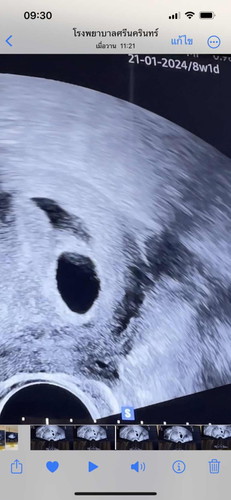

ถ้านับปจด.ขาด8วีคแล้วยังไม่เจอน้องเลยกังวลมากแม่ๆเจอน้องกี่วีคคะ ซาวผ่านช่องคลอดนัดอีก2วีคค่ะ

บ้านนี้10วีคเลยค่ะเจอหัวใจและดิ้นโชว์หมอไปเลยค่ะทำใจสบายๆค่ะแม่เดียวก็เจอน้องยังเล็กอยู่

บางคนก็เจอตอน 10w ค่ะ ถ้าไข่ตกช้า